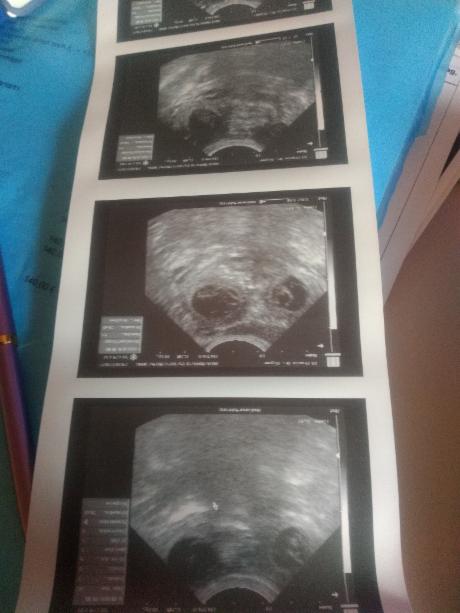

Ultraschalltermin am Tag 29:

Unsere Tierärztin meint es sind 4 oder mehr Welpen zu erwarten! Es sind einige Anfragen da, aber noch nicht alle Welpen fest vergeben.

Ultraschalltermin am Tag 30:

Wir haben 3-4 Welpen im Ultraschall gesehen!! Wir sind schon ganz gespannt. Es sind noch nicht alle Welpen vergeben!